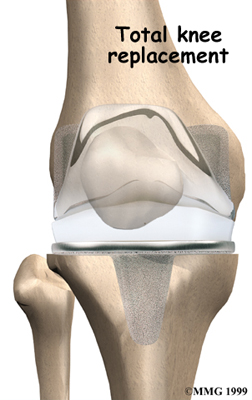

Artificial Knee Replacement

An artificial knee replacement is the ultimate solution for advanced knee OA.

Surgeons prefer not to put a new knee joint in patients younger than 60. This is because younger patients are generally more active and might put too much stress on the joint, causing it to loosen or even crack. A revision surgery to replace a damaged prosthesis is harder to do, has more possible complications, and is usually less successful than a first-time joint replacement surgery.

Related Document: FYZICAL Woodlands North's Guide to Artificial Joint Replacement of the Knee